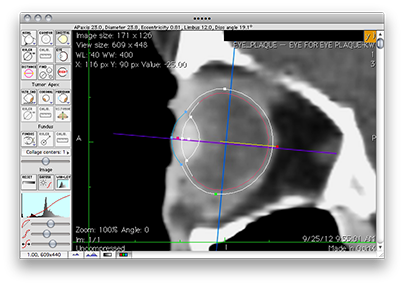

Assure that the axial image is being displayed and click the Eye button adjacent to the Calib. button to display the eye sizing tool.

• Turn off the Ruler tool. If you leave the ruler enabled it might overlap the eye in the image and interfere with your ability to interactively drag the eye sizing tool control points.

• Select left or right eye using the button just below the Eye button. The eye sizing tool orientation will adjust to the selected eye.

• Click in the middle of the eye sizing tool and drag the tool over the appropriate eye.

• Adjust the eye size to match the image by dragging the control markers. The dimensions of the eye are displayed in the status line just under the window title bar. You can enlarge the image in the vicinity of the eye using the "zoom" buttons at the lower left of the window.

• The red marker rotates the tool. The white and green markers control the diameter of the eye and lens position. The blue markers adjust the cornea & limbus. The magenta marker adjusts the ellipsoidal appearance of the anterior hemisphere of the model. The yellow lines of the tool represent an angle at the center of the PS model between the posterior pole of the eye and the center of the optic disk.

The 3D model in the setup window will change immediately in response to changes in the eye sizing tool so experiment with the tool's control handles to learn their properties. Place the Setup and Image windows side-by-side as you drag the eye sizing tool control handles to observe the behavior of the model.